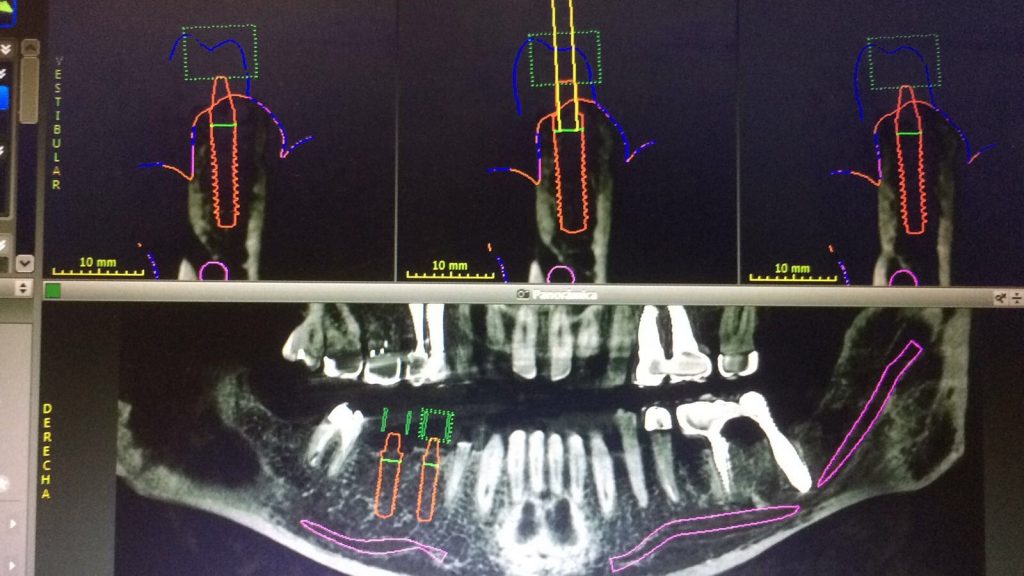

Autores: PRÓLOGO Asimismo, desde el punto de vista pedagógico, el profesional nobel en la materia tiene a su alcance la posibilidad de corregir cualquier posición implantaría en el ordenador, planear los provisionales y plasmarlos en la bio réplica antes de tocar al paciente a operar. Todos estos razonamientos nos llevan a presentar un caso de condiciones muy favorables para poner en práctica estos métodos como primer acercamiento a una Odontología Digital de alta calidad, con medios informáticos, que ya están presentes en la profesión de hoy en día, y será la protagonista única del futuro. Por otro lado, después de numerosos estudios que nos llevan a plantear el “gap” entre implante y pilar(abuttment), como principal responsable de la periimplantitis dado que la microbiota presente en el mismo es imposible de limpiar y en su presencia la cortical ósea reacciona reabsorbiéndose, nos ha llevado a utilizar implantes monobloc ya que los ejes implantarios y protéticos coincidían, y nos permitían su uso. Además, el circonio, ha mostrado a la luz de estudios muy recientes, una preservación y adhesión de los tejidos blandos superiores al titanio, tanto en su tratamiento de superficie de la rosca como a nivel gingival. DESARROLLO Paciente varón de 68 años, con antecedentes de radio/quimioterapia cinco años antes, con Rehabilitación Oral de los cuatro cuadrantes, con una Oclusión Mutuamente Compartida conservada, (REF.8) la que fracasa en el cuadrante 4, 19 años después. El mismo presentaba un puente de porcelana sobre circonio con pilares en 44 y 47, reemplazando el edentulismo de 45 y 46. Se produce la fractura del PM del 44, y ante una endodoncia antigua y corta, se decide implantar las zonas edéntulas, conservando temporariamente los pilares, hasta producida la oseointegración, para entonces también exodonciar el 44. DIAGNÓSTICO Tomamos impresiones del maxilar antagonista, Arco Facial Estático y realizamos montaje del mismo mediante la sistemática ARTEX. Producimos la relajación del músculo Pterigoideo Externo, para obtener la ORC (Oclusión en Relación Céntrica) mediante el método de Laminillas de Long, basado en el concepto de INERVACIÓN RECÍPROCA. Esto nos permitirá montar el maxilar inferior, tanto en su forma de: La primera para practicar la cirugía guiada y comprobar su eficacia, y el modelo de yeso para ser escaneado y confeccionar la GUÍA QUIRÚRGICA. La Biorréplica la obtenemos transformando los archivos DICOM que nos da el CBCT en archivos STL, y a partir de ellos, mediante una tecnología de PROTOTIPADO RÁPIDO, la obtención de un objeto físico en 3D a través de la aglutinación selectiva de una sucesión de capas de polvo. Procedemos a montar la biorrèplica y el modelo de yeso del caso. Podemos verificar la exactitud de las medidas del hueso residual en la bio réplica y compararlas con el scanner. Arrojando un resultado de 8,5 mm de cortical externa a cortical externa. Pudiendo también medir la distancia hasta el dentario. y comparar gracias a la ventana lateral de la biorréplica Dándonos 22mm de distancia. Con lo cual deducimos que implantes de 4,1mm por 12 mm serán perfectamente rodeados de hueso. Medimos también la distancia desde oclusal del antagonista, hasta el hueso desnudo. Lo mismo que, mediante la utilización de la guía radiológica, con un material radiolúcido colocado en gingival de la misma, podemos medir la altura de la encía. Con lo cual podemos calcular la altura del pilar. Es entonces cuando con el programa COC Diagnostix se realiza la programación final: Obteniendo no solo la ubicación, largo, ancho y ángulo de los implantes sino también los provisionales mediante CAD CAM. Ya entonces podemos hacer la práctica quirúrgica en la bio réplica, mediante la guía quirúrgica, instalando los implantes de prueba que no serán los de circonio, ya que la casa no cuenta con ellos, pero si otros de las mismas dimensiones. TRATAMIENTO Entramos ya en la cirugía propiamente dicha. Antisepsia de la zona a operar y zonas anexas. Comprobación del perfecto ajuste e inmovilidad de la G.Q. en boca durante la cirugía. Marcado de la encía y perforación de la cortical. Visión a través de la Guía de la mínima intervención anterior. Comprobación sin Guía. Incisión mínima mesio distal, para apartar y conservar encía queratinizada. Secuencia de drills, perforando a profundidad requerida Observación del Mínimo Trauma Implantes Strauman de Zirconio Monoblock en blíster y montádo en contrángulo reductor. Instalación controlando torque con contrángulo reductor. Comprobación clínica. Comprobación Radiográfica y con Guía. Toma de impresiones, y armado de modelos con técnicas de pasividad protética. Montaje. Resultado de las provisionales ejecutadas por CAD CAM Al no estar conformes con el resultado decidimos desechar dichas provisorias y optar por repetirlas. Nuevas provisorias realizadas mediante encerado convencional. Estado de los tejidos blandos. Provisorias en boca. Oclusión de Estímulo Inmediato. Ref.10: Carga inmediata .Alberto y Diego Bechelli. Comprobación mediante CBCT post operatorio Componentes del equipo (En la próxima presentación, mostraremos las coronas definitivas de porcelana sobre circonio, y la desoclusión provocada por una OCLUSIÓN MUTUAMENTE COMPARTIDA, sobre estos implantes y otros seis mas) REFERENCIAS

Realizamos previamente una Rx periapical Dígora (radiovisiografía) y un CBCT (TAC de haz de cono) con férula radiológica, marcando ambas raíces del 46 y la raíz del 45.

FIG: 5-6-7-8

FIG: 9-10-11-12

Fig. 9

Fig. 10

Fig. 11

Fig. 12